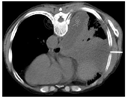

患者肺脓肿并多房包裹性脓胸诊断明确。于11月3日在CT引导下行包裹性脓胸穿刺(图7)及置管引流(图8)术。穿刺处胸水常规:深黄色、微浊胸水,无凝块,白细胞总数29×106/L,单个核细胞31%,多个核细胞69%,红细胞0×109/L,李凡他实验+;胸水生化:白蛋白25.5 g/L,球蛋白17.7 g/L,总蛋白43.2 g/L,淀粉酶40 U/L,葡萄糖7.01 mmol/L,乳酸脱氢酶556 U/L,腺苷脱氨酶17.91 U/L。胸水检验结果支持肺炎旁胸腔积液。置管处胸水常规:黄色、浑浊胸水,无凝块,白细胞总数100803×106/L,单个核细胞15%,多个核细胞85%,红细胞38×109/L,李凡他实验+++;胸水生化:白蛋白26.4 g/L,球蛋白23.6 g/L,总蛋白50 g/L,淀粉酶30 U/L,葡萄糖0.03 mmol/L,乳酸脱氢酶7020 U/L,腺苷脱氨酶130.15 U/L;胸水培养(需氧菌+厌氧菌)阴性;未查见抗酸杆菌。引流出脓性胸水约200ml(图9)。胸水检验结果支持脓胸。复查红细胞沉降率102 mm/h;血常规:白细胞计数11.9×109/L,中性粒细胞绝对值9.15×109/L,血红蛋白103 g/L,中性粒细胞百分率76.9%;C反应蛋白260.45 mg/L;肝功能:白蛋白33.5 g/L,直接胆红素26.2 umol/L,总胆红素32.4 umol/L,总胆汁酸17 umol/L;降钙素原0.69 ng/ml。予生理盐水和碳酸氢钠反复冲洗脓腔、尿激酶(1万U,1次/d)胸腔内注射,同时给予人血白蛋白静脉滴注以纠正低蛋白血症。复查胸部彩超提示右侧胸腔包裹性积液,积液黏稠,周围壁及分隔较厚。复查胸部CT(图10、图11)示:右肺上叶后段、右肺中叶及下叶多发感染并右肺下叶肺脓肿形成,右肺感染较前有所吸收;右侧胸腔引流术后,右侧胸腔积液、积脓较前吸收减少;右侧胸膜增厚。于11月8日再次在CT引导下行包裹性脓胸穿刺术。患者临床症状逐渐改善,11月17日复查红细胞沉降率96 mm/h;血常规:白细胞计数7.89 ×109/L,中性粒细胞绝对值4.53×109/L,血红蛋白104 g/L,中性粒细胞百分率57.4%;C反应蛋白25.75 mg/L;白蛋白40.8 g/L;降钙素原正常。11月22日复查胸部CT(图12,图13):右肺下叶见片状、不规则状密度增高影,部分可见液化坏死,较前片吸收好转;右肺底局限性包裹性积液;双肺下叶、右肺中叶感染;右侧胸膜弥漫性增厚,右侧胸腔包裹性积液;右侧斜裂少许包裹性积液;纵隔淋巴结肿大。11月23日复查红细胞沉降率60 mm/h;血常规:白细胞计数5.57×109/L,中性粒细胞绝对值2.76×109/L,血红蛋白106 g/L,中性粒细胞百分率49.6%;C反应蛋白11.93 mg/L;电解质正常。患者病情好转于11月24日出院,继续口服莫西沙星和甲硝唑抗感染治疗1个月。

12月24日复查胸部CT提示双肺感染、右肺下叶脓肿较前片吸收;右肺底局限性包裹性积液、右侧胸腔包裹性积液和右侧斜裂少许包裹性积液较前片减少(图14、图15)。2022年3月2日患者来院复诊,诉体重增加约5 kg,无明显不适,复查胸部CT(图16,图17,图18)提示右下肺脓肿已吸收,双肺下叶慢性感染、纤维化灶。